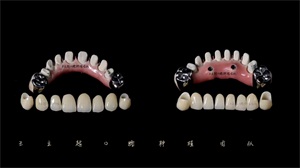

另一方面,我们在进行取模的过程中,发现彭阿姨很容易恶心干呕,采用传统取模的方式非常困难,所以决定利用数字化口扫取研究模,3D打印牙模。在克服种种阻碍因素后,由王立超带领的种植团队终制定出彭阿姨的种植方案——上下颌都采用All-on-4种植技术进行全口种植修复。在进行充分的沟通后,彭阿姨及其家人也同意了该方案。

经过一段时间的愈合修复,终于迎来了戴牙的日子,彭阿姨告诉我们她既兴奋又激动,昨晚一整宿都没睡着,因为马上就有一口新牙齿了。彭阿姨戴上稳固舒适的新牙齿后,开心的笑了,她说:“终于可以扔掉佩戴多年的活动牙了,它实在是给我的生活带来了太多不便,有了新牙我以后就可以大口吃肉,吃很多以前想吃却不能吃的美食”。

戴牙之后彭阿姨满脸的笑容和连声的道谢让我们种植团队感到格外骄傲和满足。佩戴十几年的活动牙不仅会给患者的生活带来不便,更会影响到患者的心理,会造成负面情绪的累积。牙医的职责就是为患者解决口腔难题,让他们心情愉悦享受更高质量的生活。东莞口腔医院种植科为更好服务地缺牙患者,率先迈进数字化种植牙时代,拥有精湛的临床技能、良好的医德医风和创新的科研精神,今日彭阿姨成功的戴牙故事又为医患相互成就画上浓墨重彩的一笔。